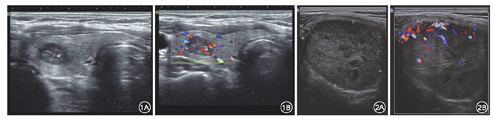

所有甲状腺髓样癌结节中93.1%(67/72)为实性,87.5%(63/72)低回声,69.4%(50/72)形态规整,76.4%(55/72)边界清晰,48.6%(35/72)有钙化(以微小钙化为主,62.9%),62.5%(45/72)纵横比(A/T)<1,57%内部有血流(血流丰富者为主,68.3%,28/41)(图1,图2)。55例患者有颈部淋巴结检查描述,40例发现颈部淋巴结肿大,最终术后病理证实为淋巴结转移者25例,超声诊断准确率62.5%(25/40)。

90个切除的结节中,术前超声诊断为可疑恶性结节52个、良性结节38个。由表2可见边界不清晰(30.8%比10.5%,P=0.023)、形态不规整(36.5%比13.2%,P=0.013)和颈部淋巴结异常肿大(82.7%比39.5%,P=0.000)更多见。根据术后病理分组,比较于自身良性结节,髓样癌结节钙化率更高(48.6%比5.6%,P=0.001)和内部血流丰富更多见(38.9%比16.7% ,P=0.030)。形态规整是甲状腺良性结节的常见超声影像特点。本研究中69.4%(50/72)髓样癌结节表现为形态规整,但自身良性结节中形态规整者更多见(94.4%比69.4%,P=0.030)。结节质地、回声类型、边界、纵横比等方面,两组之间差异无统计学意义(表1)。